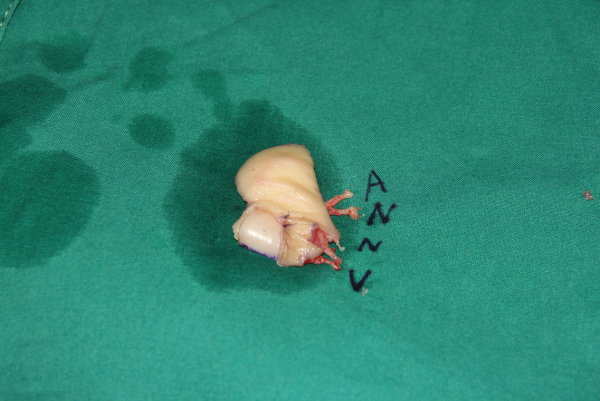

前天值班,来了7个再植的病人,初学者来省立医院进修是个很好的选择。这是其中一个。示指旋转撕脱,近侧指间关节处离断,保关节再植。

非断面截骨